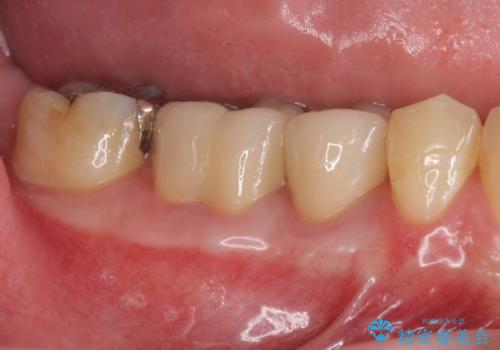

エムドゲインを用いた歯周病再生治療

今回治療前は歯周ポケットの値は7mmと、中〜高度の歯周病の状態でしたが、エムドゲインを用いた歯周病再生治療を行うことで、歯周ポケットは3mmまで回復し出血もなく良好な状態を維持しています。

歯周ポケットが再発しないよう、定期的なメンテナンスとチェックが大切です。